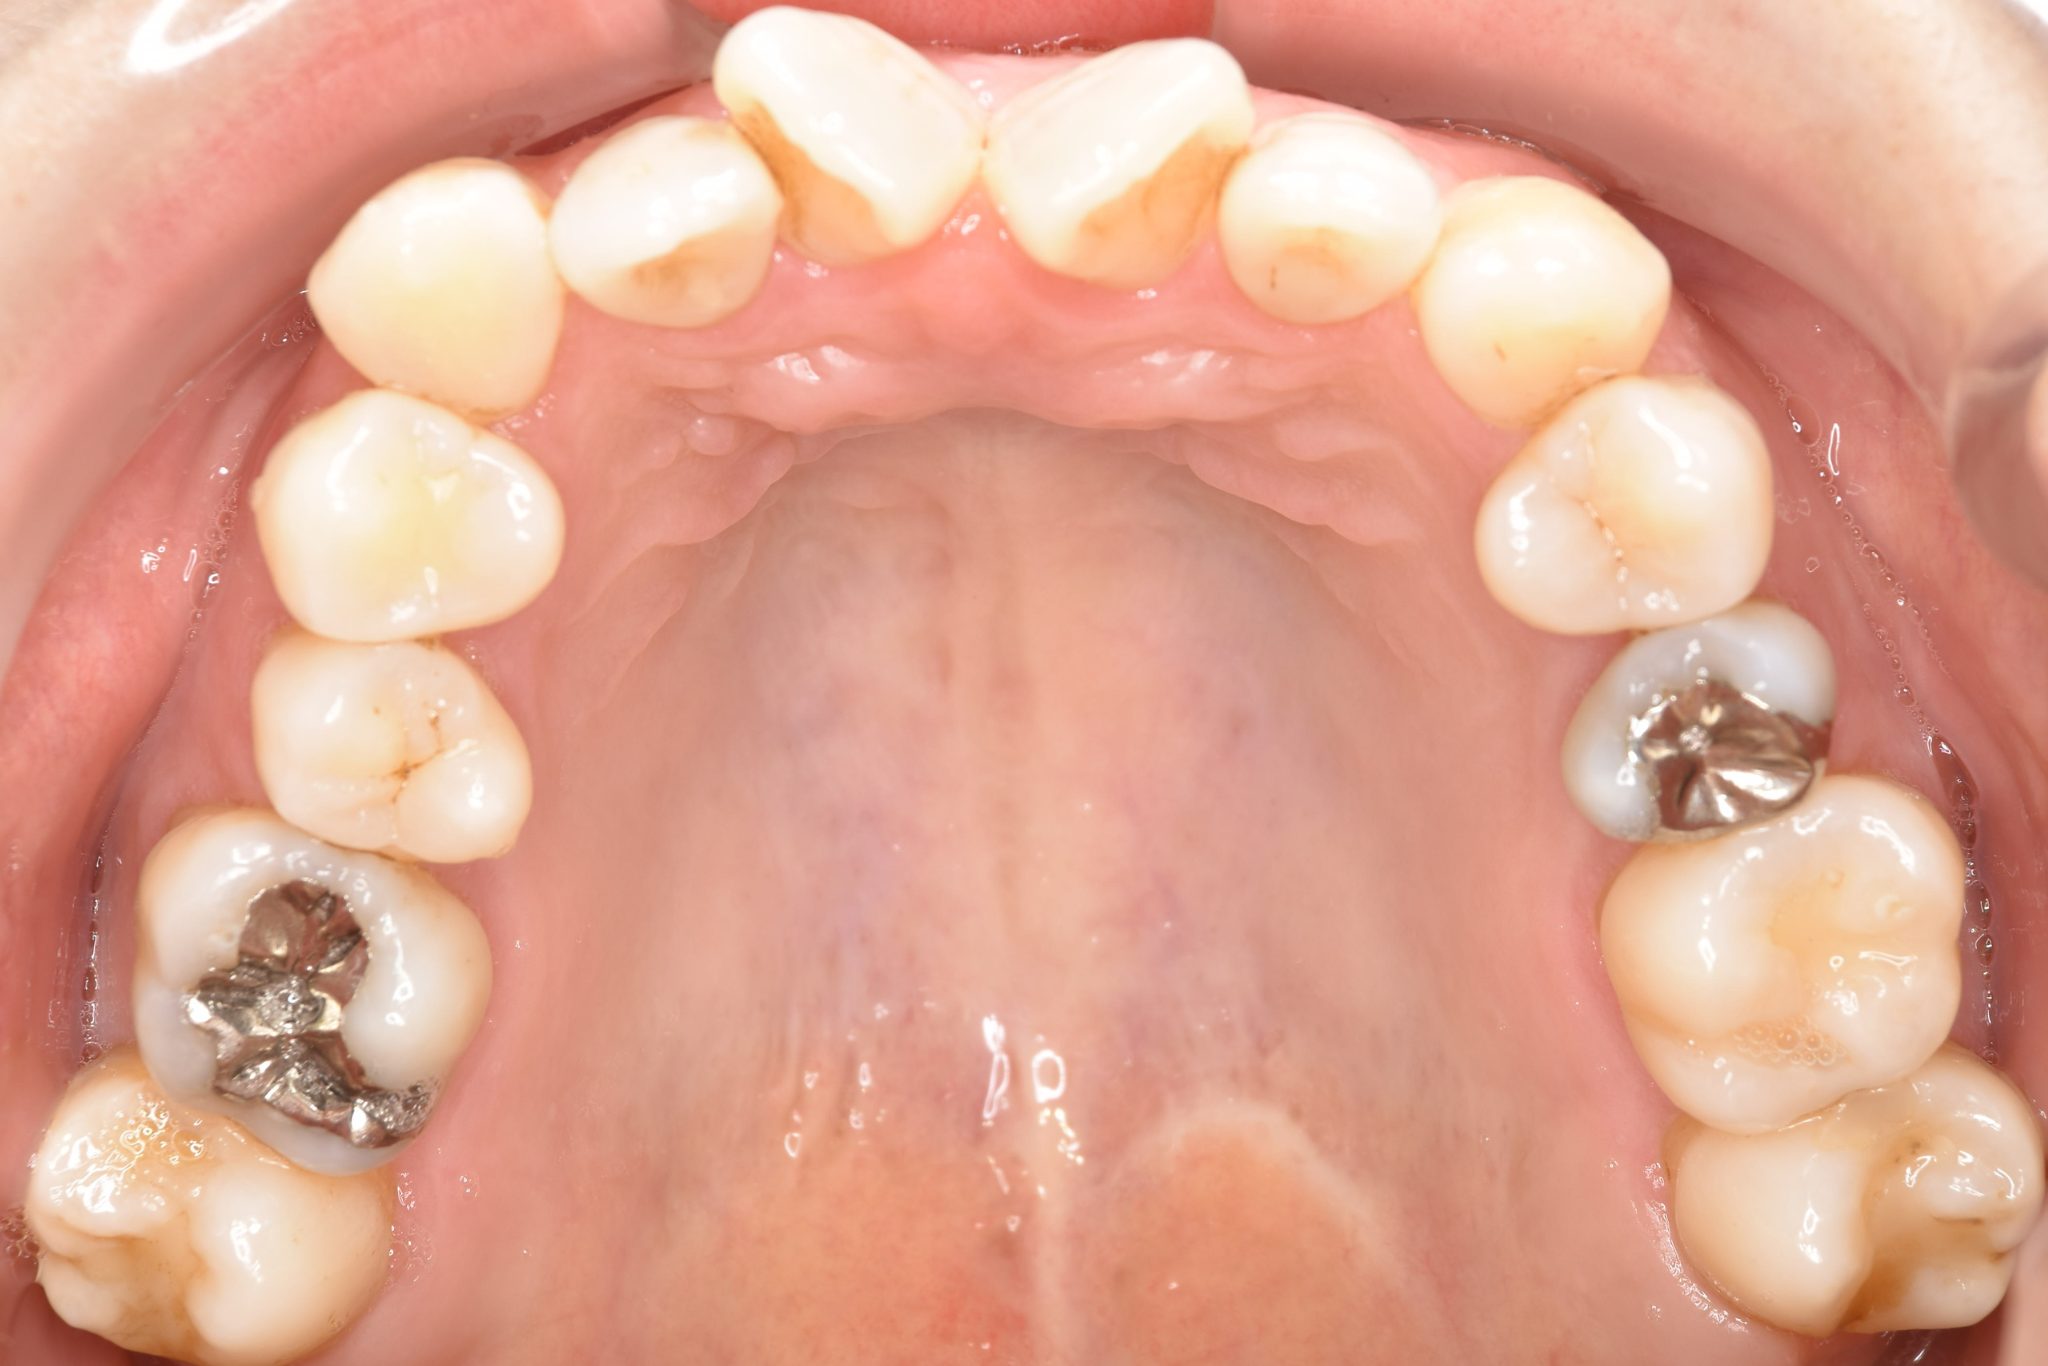

ビフォー

保険での矯正治療|症例_138